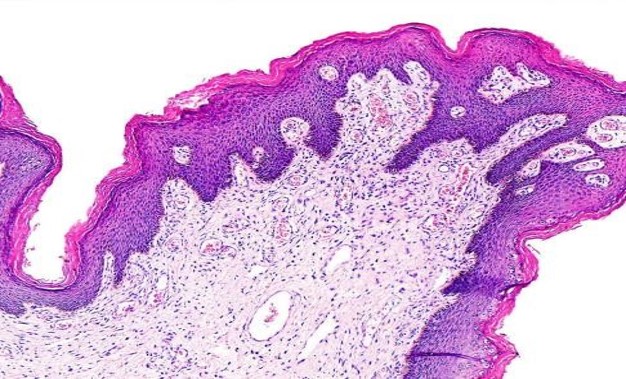

Esta solución ha sido fundamental en la revolución de la histología a nivel global, permitiendo diagnósticos más rápidos y precisos y optimizando los flujos de trabajo. Se ha demostrado que SYNAPSE Pathology es capaz de entregar imágenes digitales para diagnóstico 1,7 horas más rápido que las tradicionales muestras en vidrio.

El enfoque de Fujifilm, basado en la nube y neutral en cuanto a proveedores, ha permitido a la compañía adaptarse a las necesidades específicas de sus clientes en España. De hecho, la arquitectura abierta de SYNAPSE Pathology facilita la compatibilidad con cualquier escáner y proveedor de sistemas de información de laboratorio (LIMS), lo que asegura la interoperabilidad y protege las inversiones de los laboratorios en el futuro.